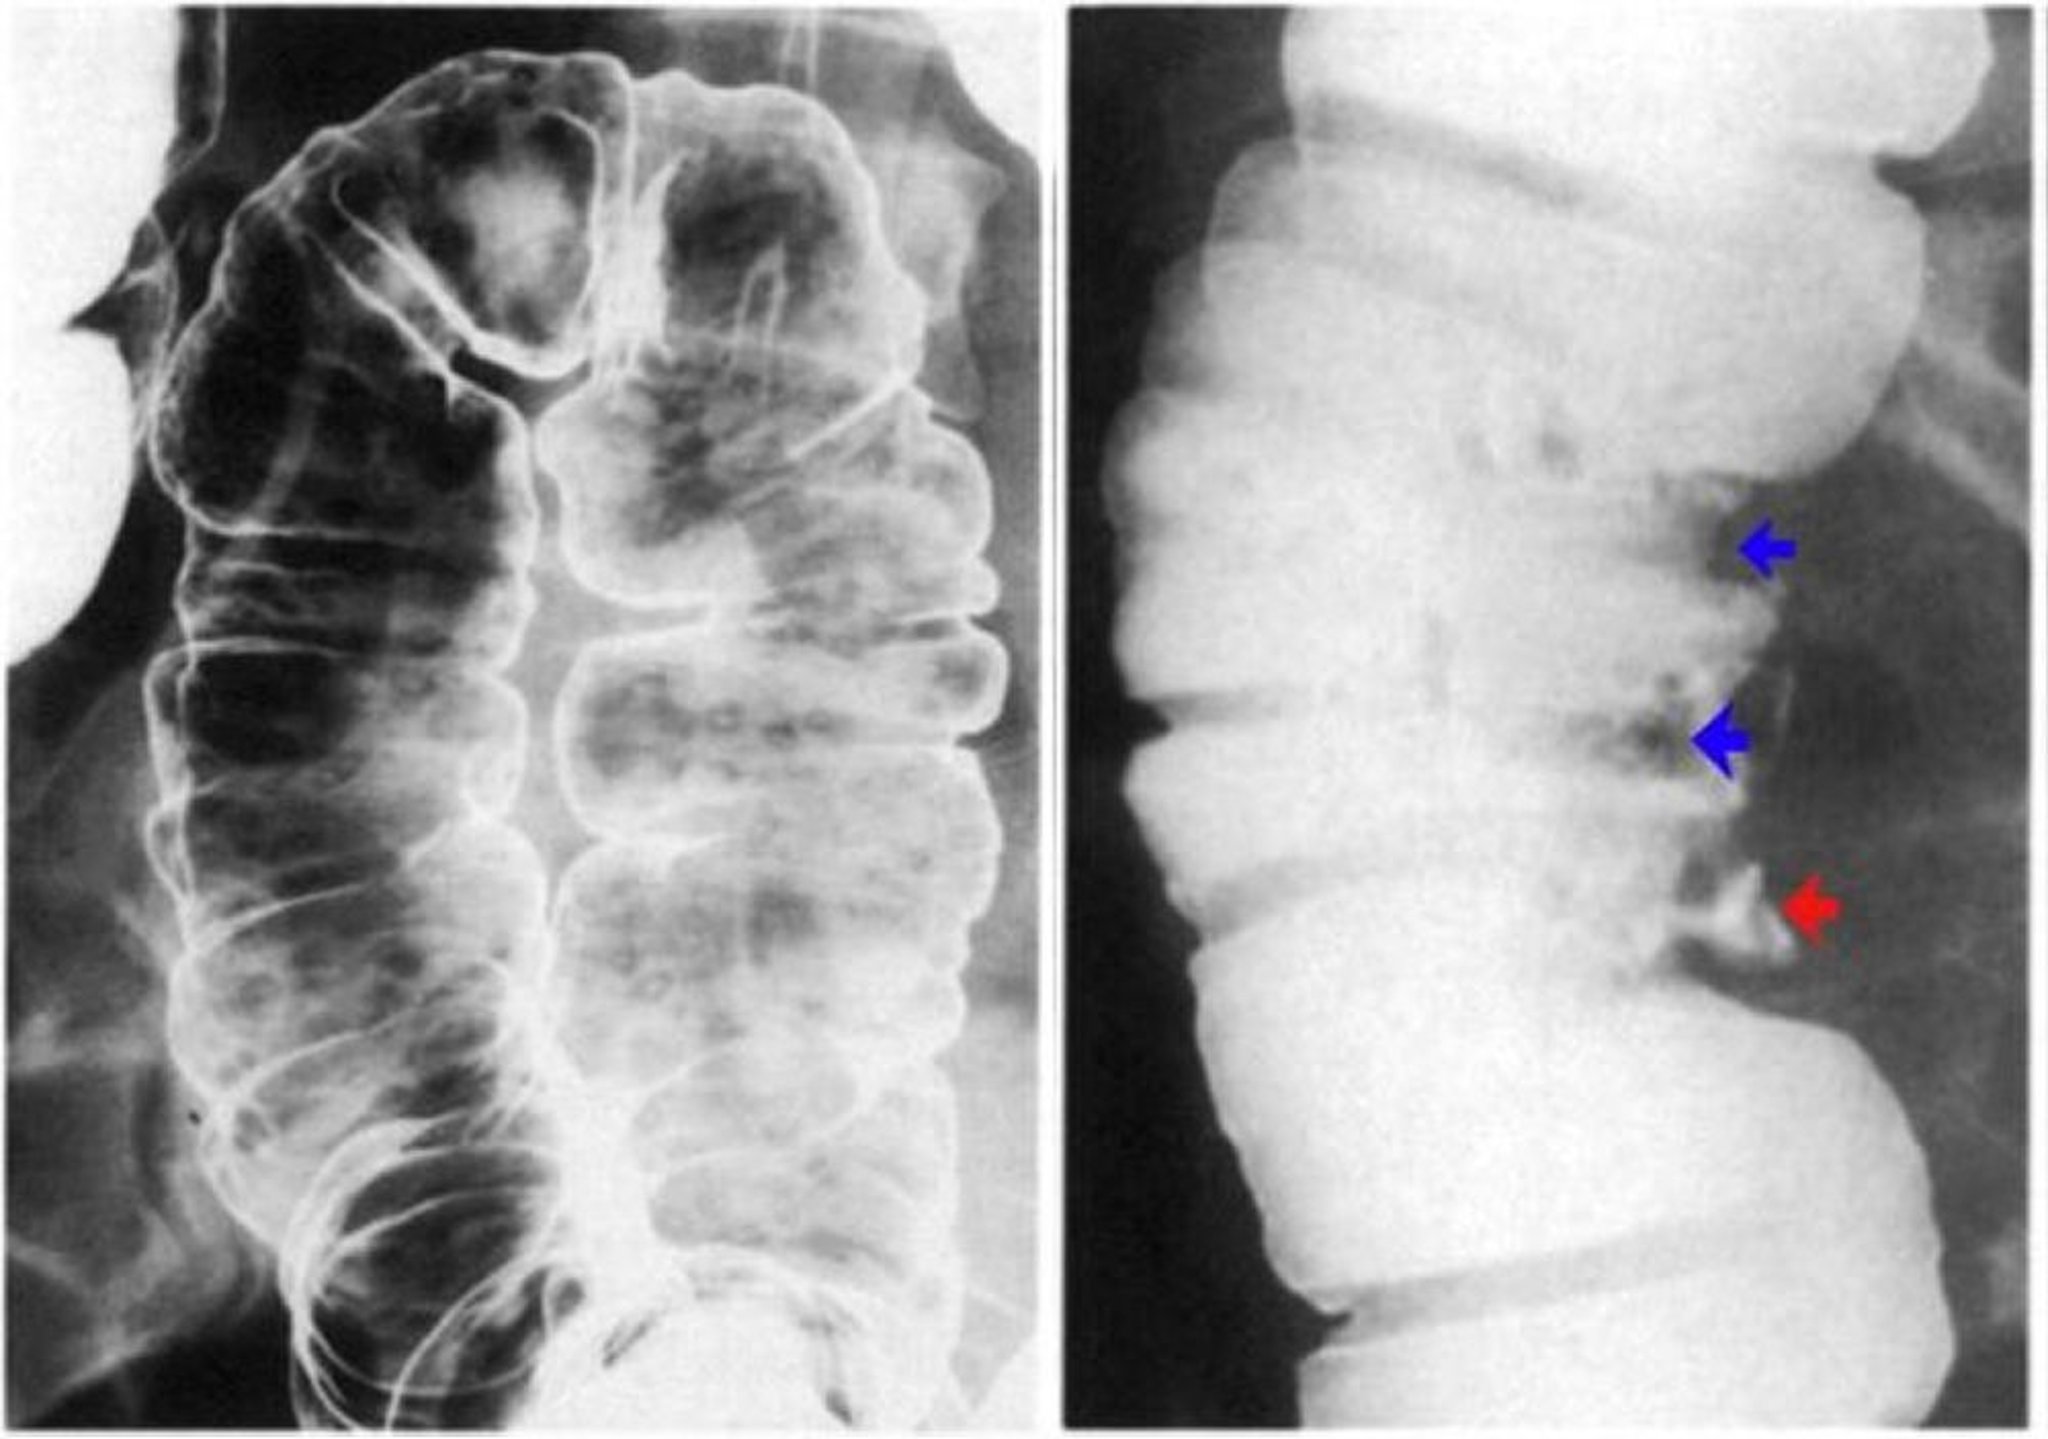

Іригографія з барієвою клізмою демонструє наявність виразкування стінки товстої кишки

The left image shows aphthous ulcers. There are discrete erosions with a lucent halo on a background of normal mucosa. The right image shows pseudopolyps demonstrated by contrast defects (blue arrows) and also a deep ulcer (red arrow).